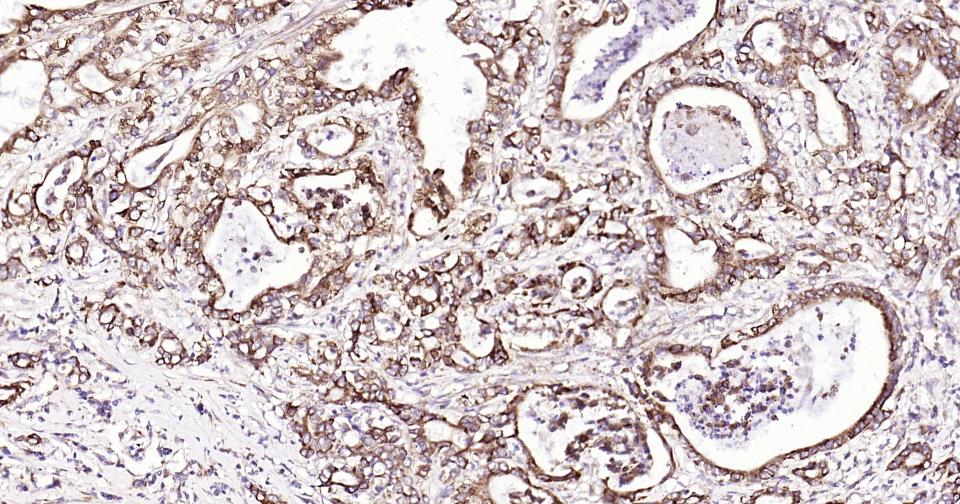

Paraformaldehyde-fixed, paraffin embedded Human Kidney; Antigen retrieval by boiling in sodium citrate buffer (pH6.0) for 15 min; Antibody incubation with Shh Monoclonal Antibody, Unconjugated(bsm-61111R) at 1:200 overnight at 4°C, followed by conjugation to the SP Kit (Rabbit, SP-0023) and DAB (C-0010) staining.